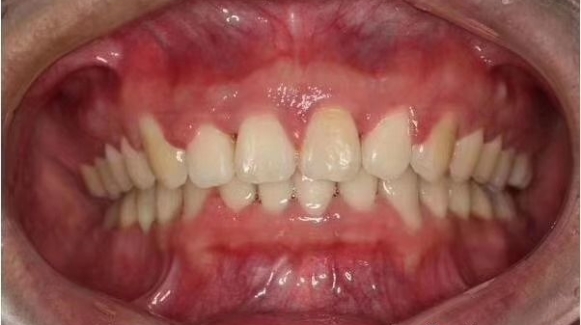

前牙深覆盖的临床表现及治疗原则 前牙深覆盖是指上前牙切缘至下前牙唇面的最大水平距离大于3mm者。是上下牙弓近远中关系的异常,大多开始发生于替牙期和恒牙早期,可能单纯为前牙深覆盖,磨牙关系正常,... 牙齿矫正 仪捷 898 2024-03-14

前牙深覆盖的病因是什么 前牙深覆盖有哪些临床表现 前牙深覆盖指上前牙切端至下前牙唇面的最大水平距离超过3mm者,是一种常见的错颌,磨牙关系多为远中颌,并常伴有前牙深覆颌,是典型的安氏Ⅱ类Ⅰ分类错颌。... 牙齿矫正 吴芳芳 906 2023-12-28